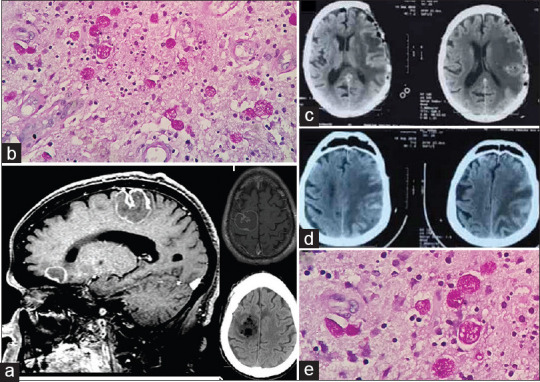

Hình ảnh chụp não của một ca bệnh áp xe não do amip.